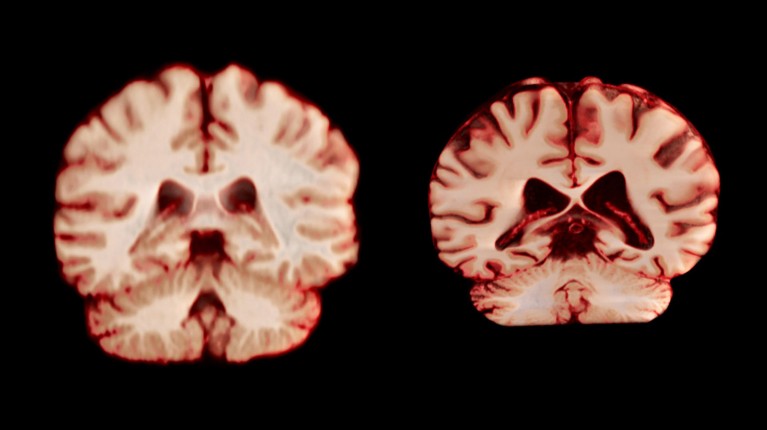

Здрав мозак (лево) и мозак који су погођени Алзхеимеровом болешћу. КРЕДИТ: Анатомски путопис / СПЛ